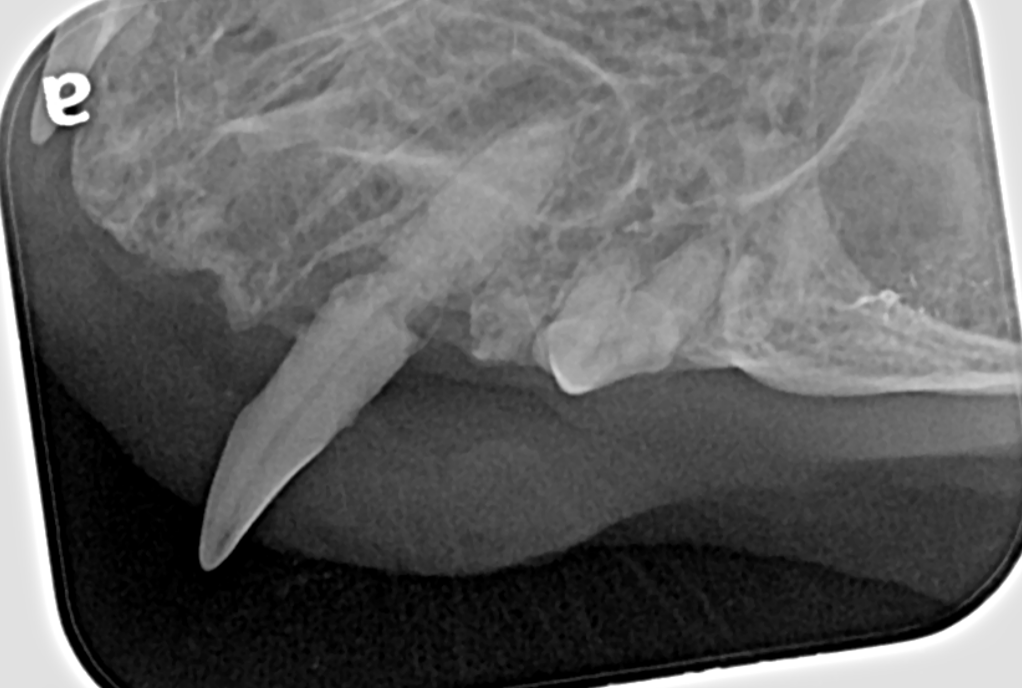

Dental radiograph (x-ray) of the same tooth showing a combination of periodontal bone loss and tooth resorption, seen as loss of tooth structure.